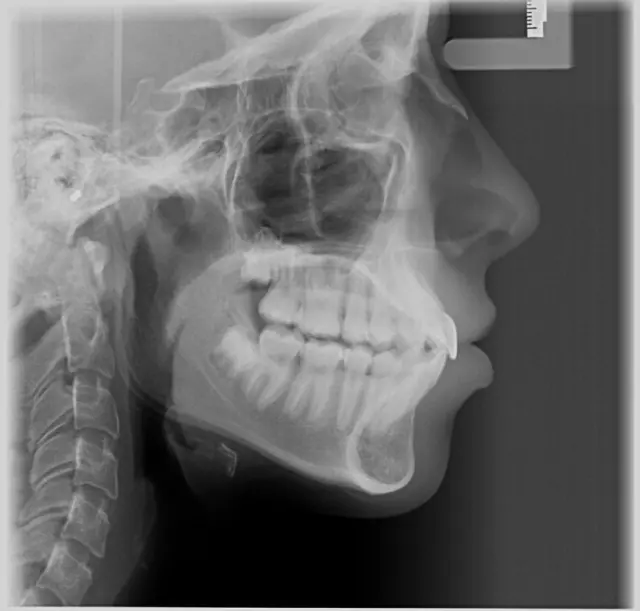

U našoj ordinaciji stremimo ka pružanju najkvalitetnije dentalne nege, a jedna od ključnih usluga koju nudimo je ortopan snimak.

Kako bismo osigurali tačnu dijagnozu i pravilno planiranje terapije, naš tim koristi najmoderniju opremu i tehnologiju prilikom izrade ortopan snimka.

Uz pomoć ortopana, možemo otkriti potencijalne probleme poput karijesa, upala korena zuba, cisti, tumora ili nepravilnog rasta zuba pre nego što postanu ozbiljni.

Za najpreciznije ortopan snimanje zuba sa minimalnim zračenjem i vrhunskim kvalitetom - posetite nas!